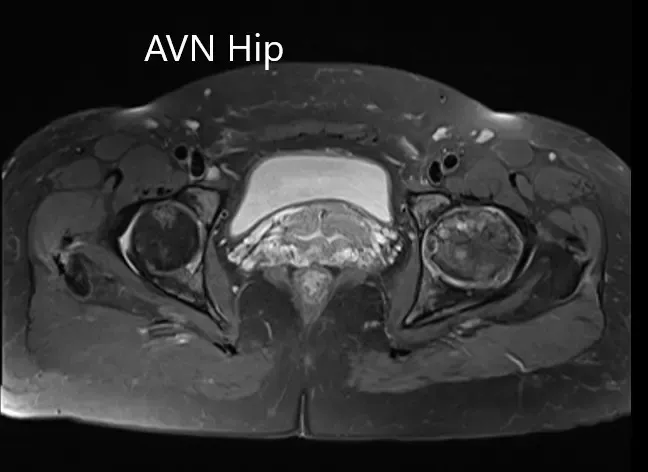

Se realizó una resonancia magnética que mostró una intensidad de señal alterada tanto en T1WI como en T2WI. Hubo un colapso sutil de la cabeza femoral izquierda. Se observó una línea sérpinosa e hiperintensa en T2WI que delimitaba una zona de osteonecrosis en la cabeza femoral izquierda. Esta zona afectaba al compartimento lateral y medial y cubría más del 50% de la superficie de la cabeza.

Se visualizaron cambios osteoartríticos secundarios en forma de reducción del espacio articular anterosuperior y formación de osteófitos. Se observó una pequeña cantidad de líquido en la cavidad articular.

T1WI y T2WI de la resonancia magnética muestran una sección axial de la cabeza femoral bilateral.